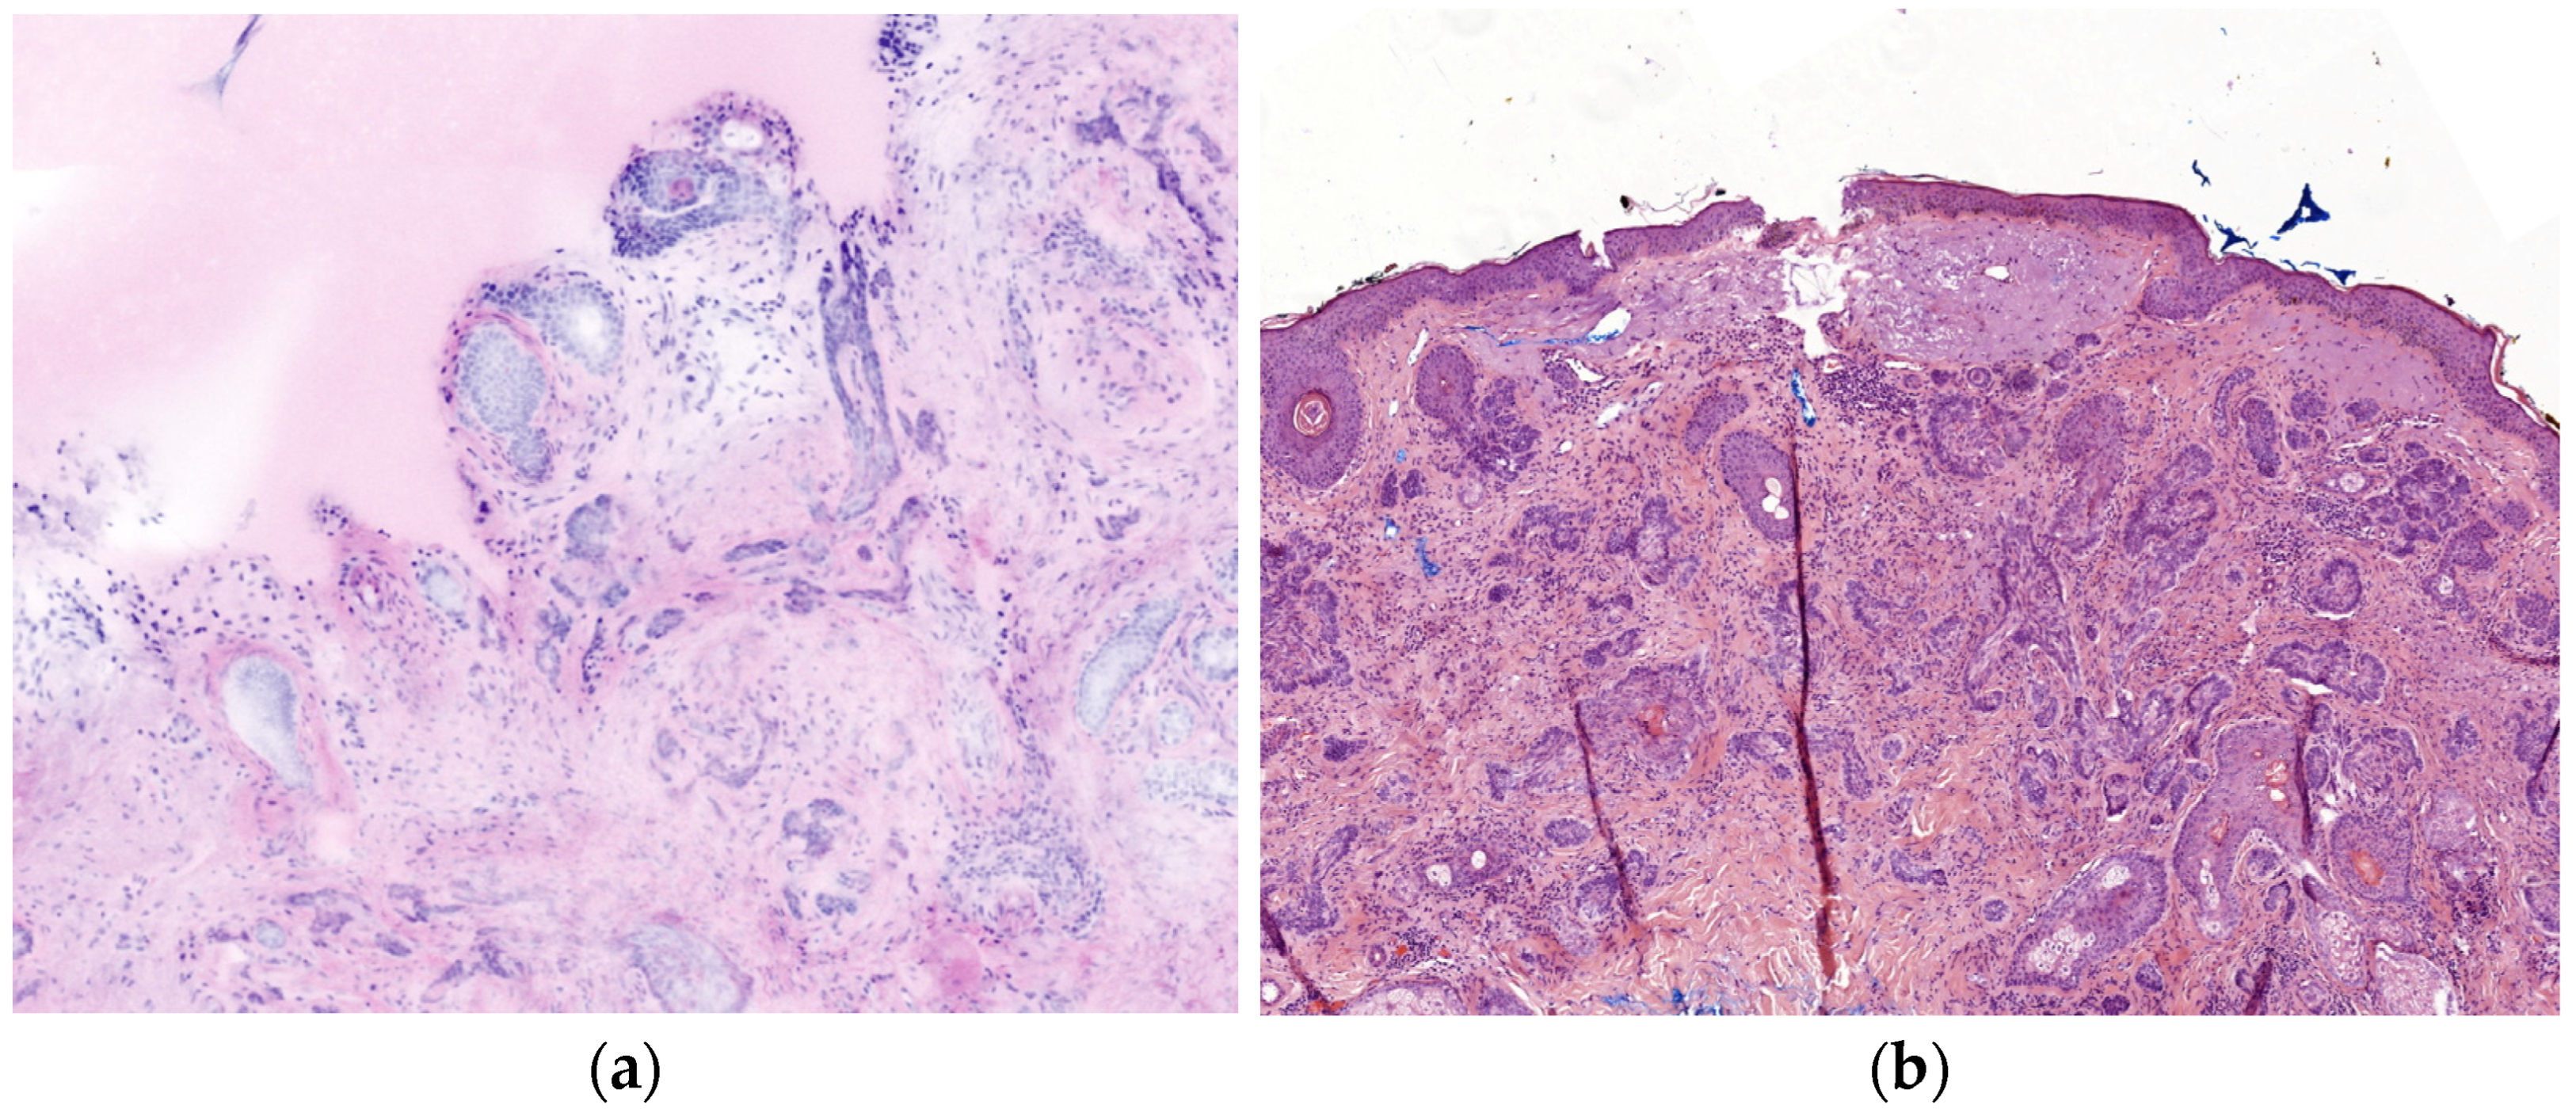

Residual NMSC tumor parts in the lateral surgical margin, especially BCC, are often found superficially, directly on the underside of the epidermis, and have a limited penetration depth, making epidermis visibility essential for re-excision diagnosis. Visualizing the epidermis completely by evRCM is difficult, and its assessment requires experience. While the epidermis is stiff, the dermis and subcutaneous fat tissue are softer and more flexible. Once the tissue is clamped between the glass panes, the laterally overlying epidermis often tilts inwards or outwards and can either not be seen at all or obscure parts of the sub-epidermal dermis, crucial for superficial tumor remnant diagnosis (Figure 3). This effect is intensified if the post-excise is cut round or unevenly. Fixing the tissue with a sponge, molded plasticine, or a splint could help protect the exact position of the epidermis. Moreover, the position under the cover glass can be corrected with a scalpel. Despite these methods, complete visualization of the epidermis is often impossible. In this study, the epidermis was moderately or poorly visible in six of the eight cases with a false-negative diagnosis of tumor-free surgical margins. Limited image quality due to air bubbles and rolling or incompletely adherent epidermis has also been reported as a problem with evRCM [27,28,32,37]. Preparation requires some time and experience. The operation is significantly extended if the operating surgeon also prepares, acquires the images, and diagnoses using evRCM. If possible, an experienced physician assistant should carry out tissue preparation and evRCM imaging.

Figure 3. The epidermis often tilts inwards or outwards when clamped between the glass panes. (a) The bright stripe marked by the red arrow is the inward-tilted epidermis. Consequently, the epidermis is barely visible in the evRCM image (b), and the subepidermal areas might be obscured.

Figure 4. Comparison of a sclerodermiform BCC between evRCM and pathology. (a) Due to the lower contrast and the lack of epidermis, it is difficult to distinguish between sclerodermiform tumor nests and skin adnexal structures in the evRCM images. (b) The sclerodermiform BCC is easy to recognize on the histological slide.